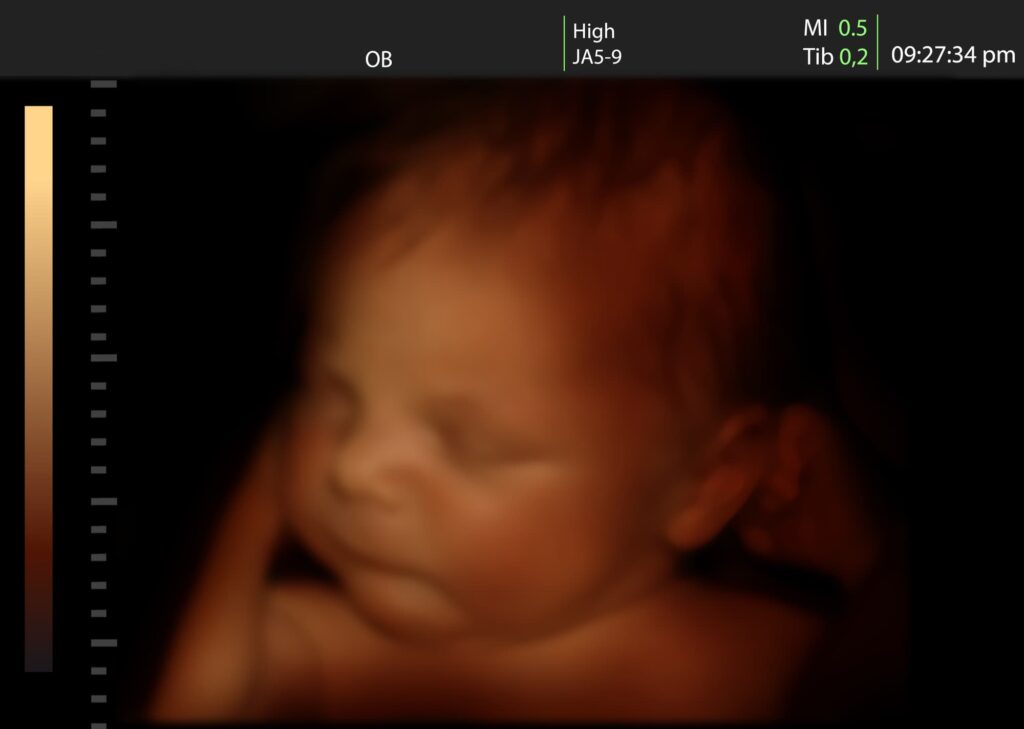

Echografie in 3D bestaat uit stilstaande beelden. Een 3D-echo wordt uit meerdere 2D-beelden opgebouwd. Hierdoor is het mogelijk je kind in perspectief en in kleur te zien.

3. 4D- pretecho

Een 4D echo zijn bewegende 3D beelden in kleur. Een 4D echo wordt ook wel ‘live 3D’ genoemd. Het gaat hierbij om real-time bewegende beelden. Met de 4D techniek kun je dus vaak ook gelaatsuitdrukkingen van je baby zien en misschien zie je je baby wel glimlachen, gapen of op zijn duim zuigen.

Wil je bolle wangetjes zien? Dan is dit het moment. Vanaf ongeveer 25 weken begint je baby een vetlaagje te krijgen. Misschien heeft je baby kuiltjes in zijn kind of een wipneusje. Met een 3D echo kan je goed alle details zien.